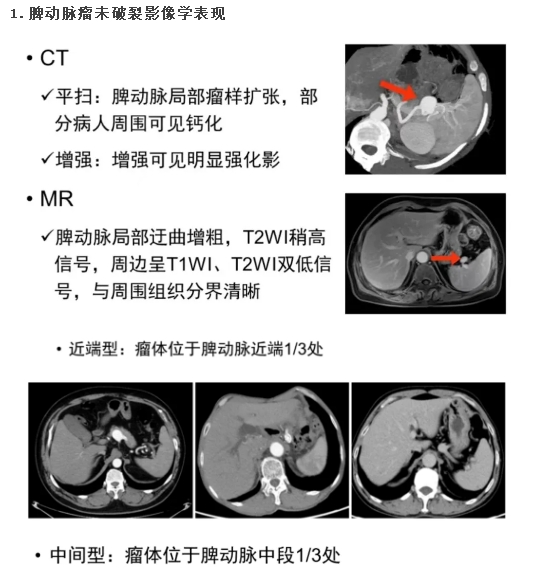

(1)脾动脉瘤未破裂影像学表现